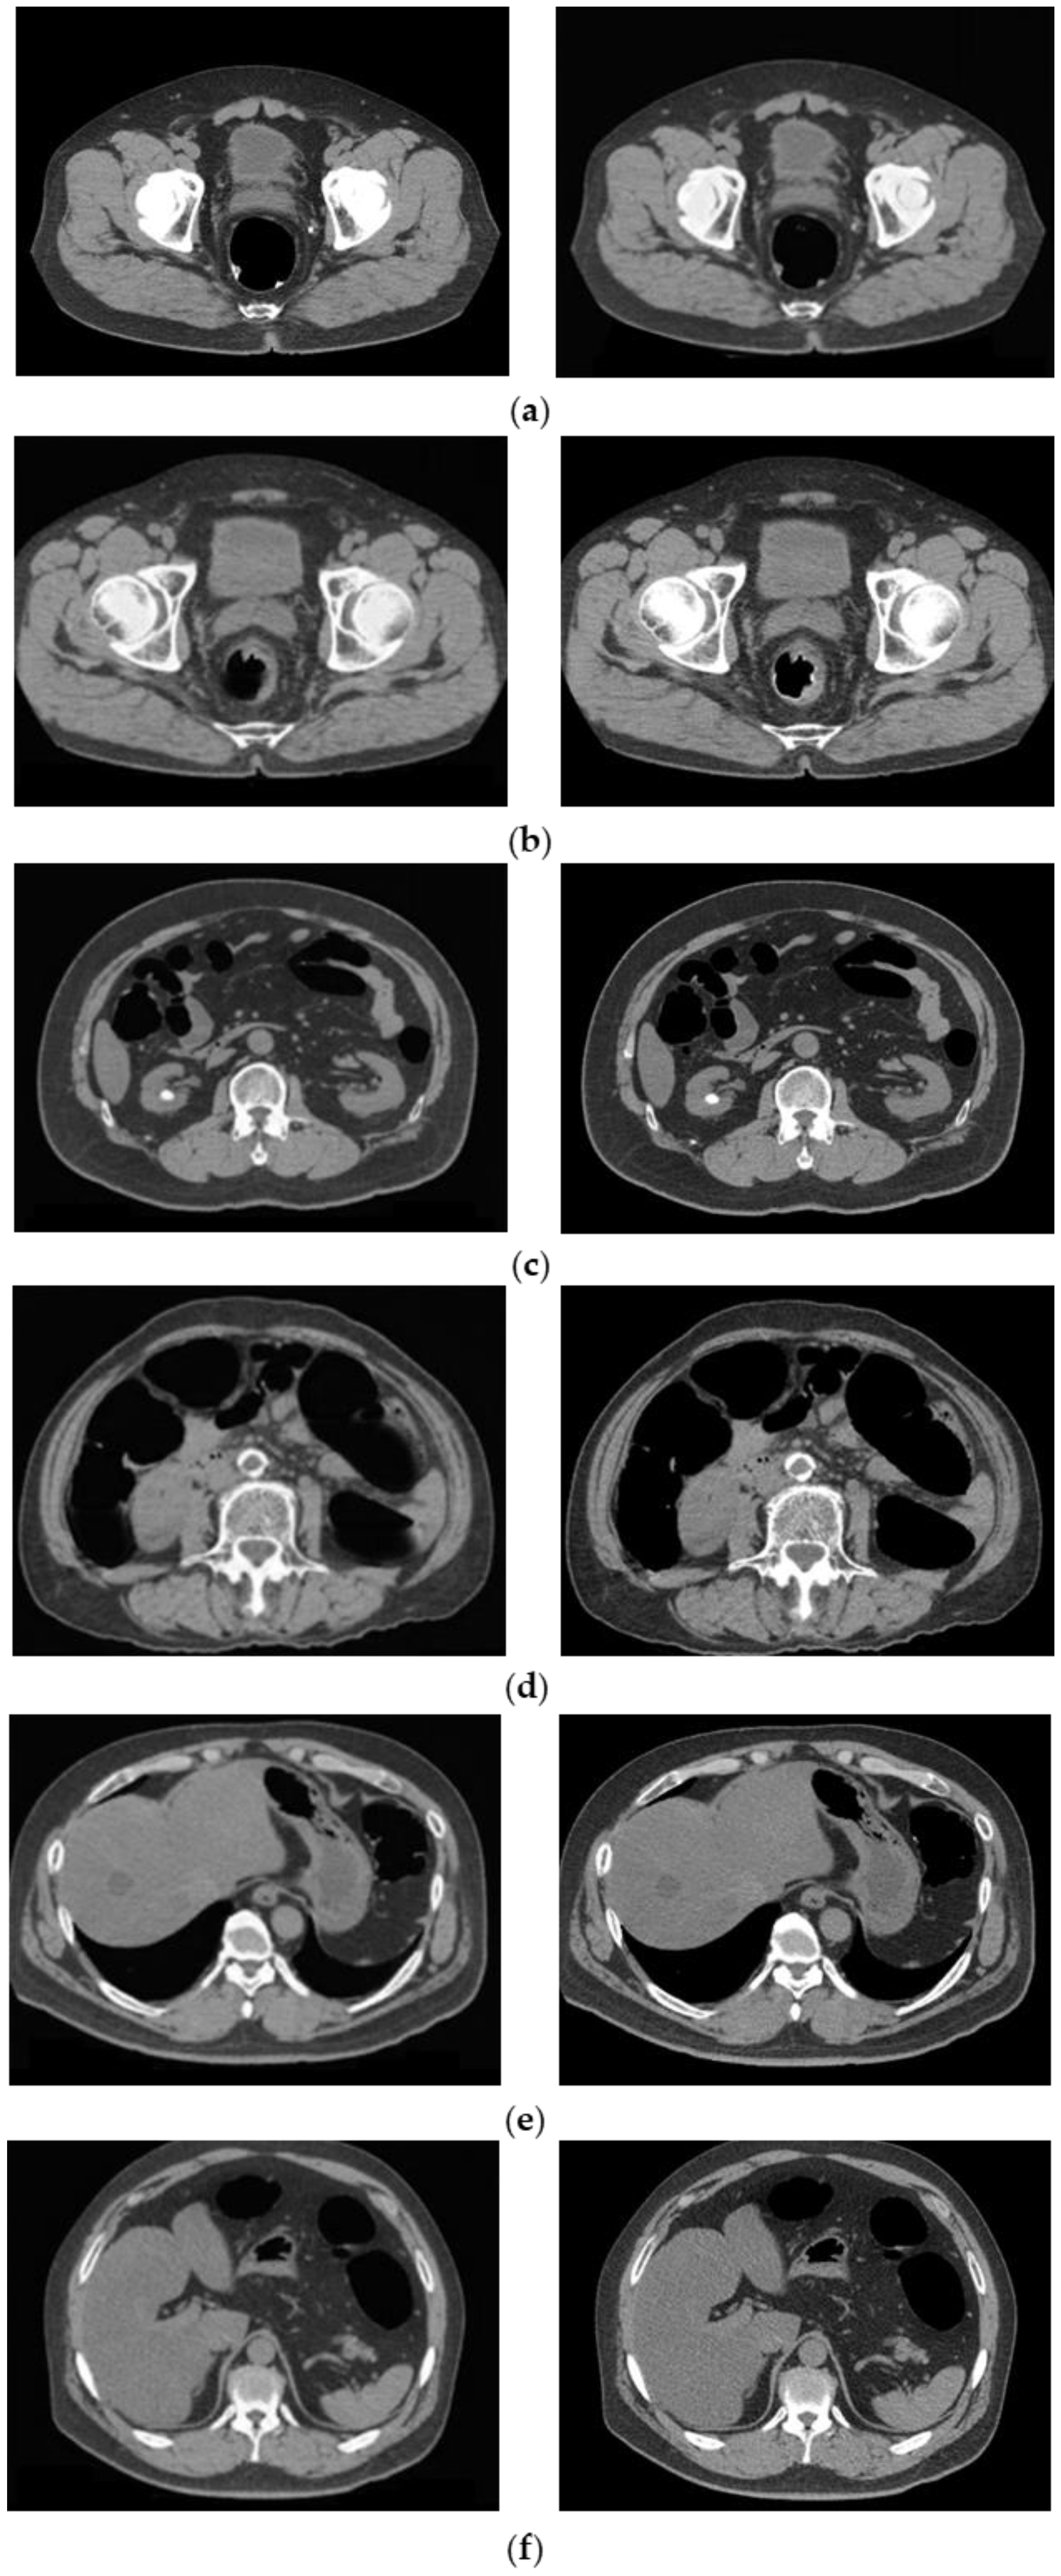

3.1. Cleansing Images Generated Using CycleGAN

4.1. Images Generated by CycleGAN